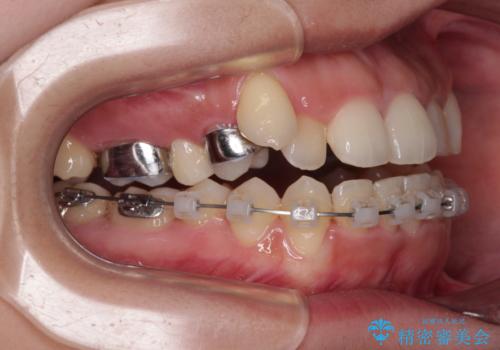

- クリアブラケット

上顎の急速拡大装置を使用して上顎骨を側方に拡大することで上顎歯列を拡大し、下顎歯列も拡大できるようにすることで、歯列を整えることとしました。

歯列矯正では基本的に骨格を改善することはできませんが、急速拡大装置(MARPE)を使用することで上顎骨を側方に拡大させることができ、咬合状態を大きく改善することができます。